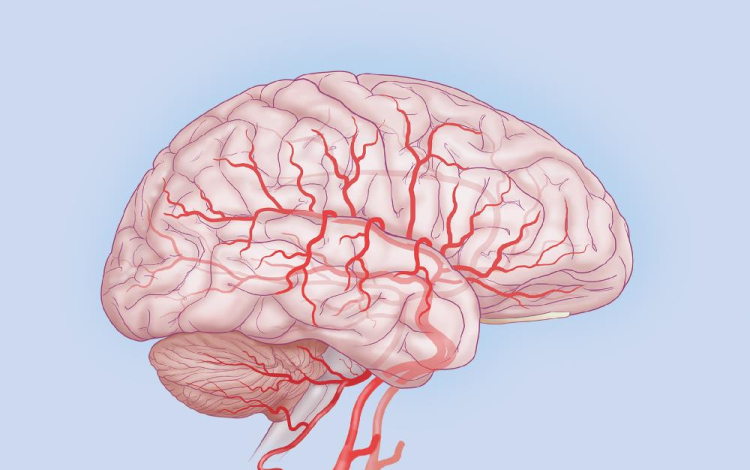

A Stanford Egyetem kutatói rohamok során jelentkező agyi aktivitást konvertáltak zenévé.

Dr. Josef Parvizi neurológus és Chris Chafe professzor, zenekutató mintegy száz elektróda segítségével regisztrálta a rohamok során keletkező agyi aktivitást, és a mintázatot zenévé alakították át. Az egyes hullámokhoz az emberi hangtartományhoz közeli hangjegyeket rendelve jutottak el az agy zenéjéig.

A módszer során a hagyományos módszert jelentő eeg-vel térképezték fel a normál aktivitás, illetve a görcsroham során jelentkező elektromos hullámokat, melyek az idegsejtek kisülése miatt jönnek létre.

A módszer jelentősége túlmutathat egy érdekes kutatáson, ugyanis az így kapott hallgatózási lelet alapján könnyűszerrel el lehet különíteni a rohamos aktivitást a normál működésre jellemzőtől. A kutatók szerint az „agyi sztetoszkóp” az epilepsziás betegek diagnosztikájában jelent pontosabb alternatívát. A fejlesztés az egyetem Bio-X Interdiszciplináris Programjának keretein belül zajlott, mely 2000 óta fut, és mintegy 141 tudóst foglalkoztat.